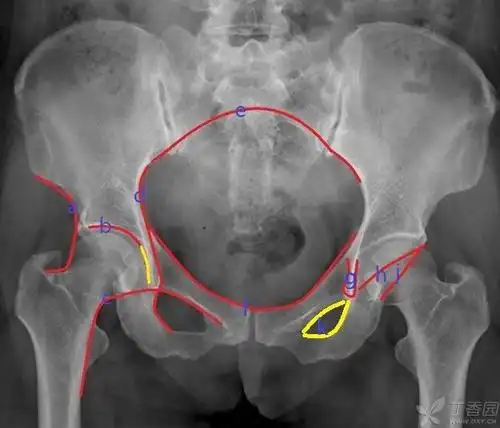

专题讲座ppt:骨盆x线解剖